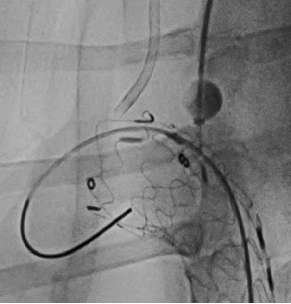

case 1

患者男性,51岁,主动脉夹层,通过Futhrough系统完成左锁骨下动脉(LSA)原位开窗重建。术中使用可调弯鞘(Fustar)和破膜系统,DSA显示破膜即刻成功,术后分支通畅,无并发症。

术前造影

穿刺破膜

球囊后扩

术后造影